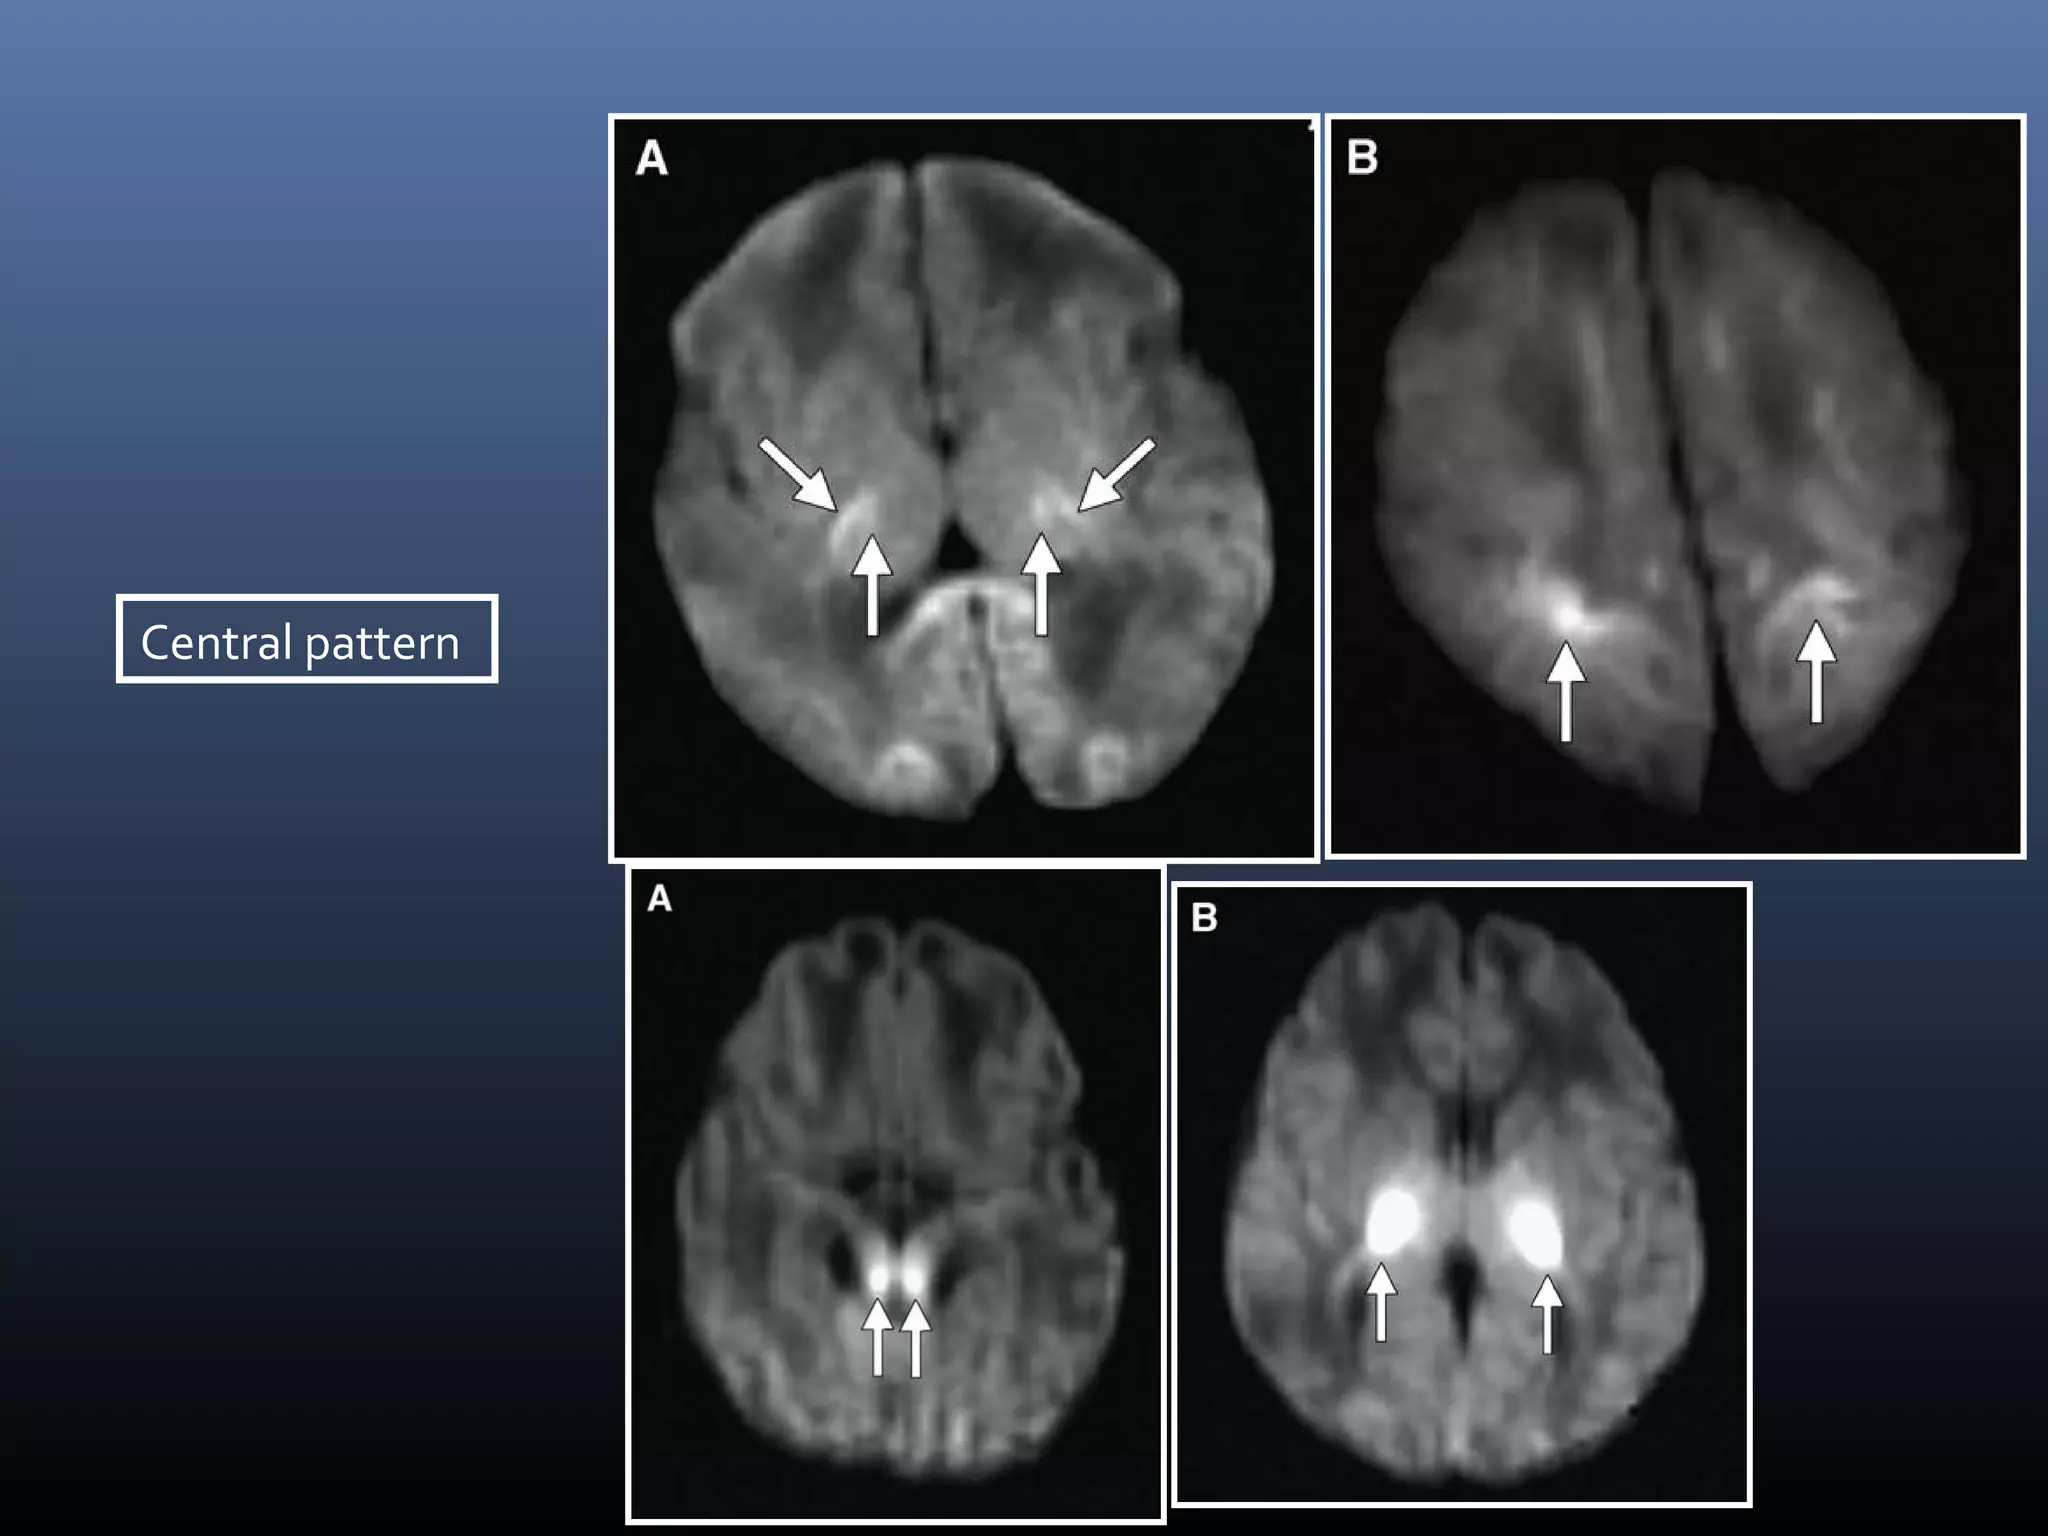

Central- Basal ganglia, Ventrolateral thalami, Brainstem

Central pattern